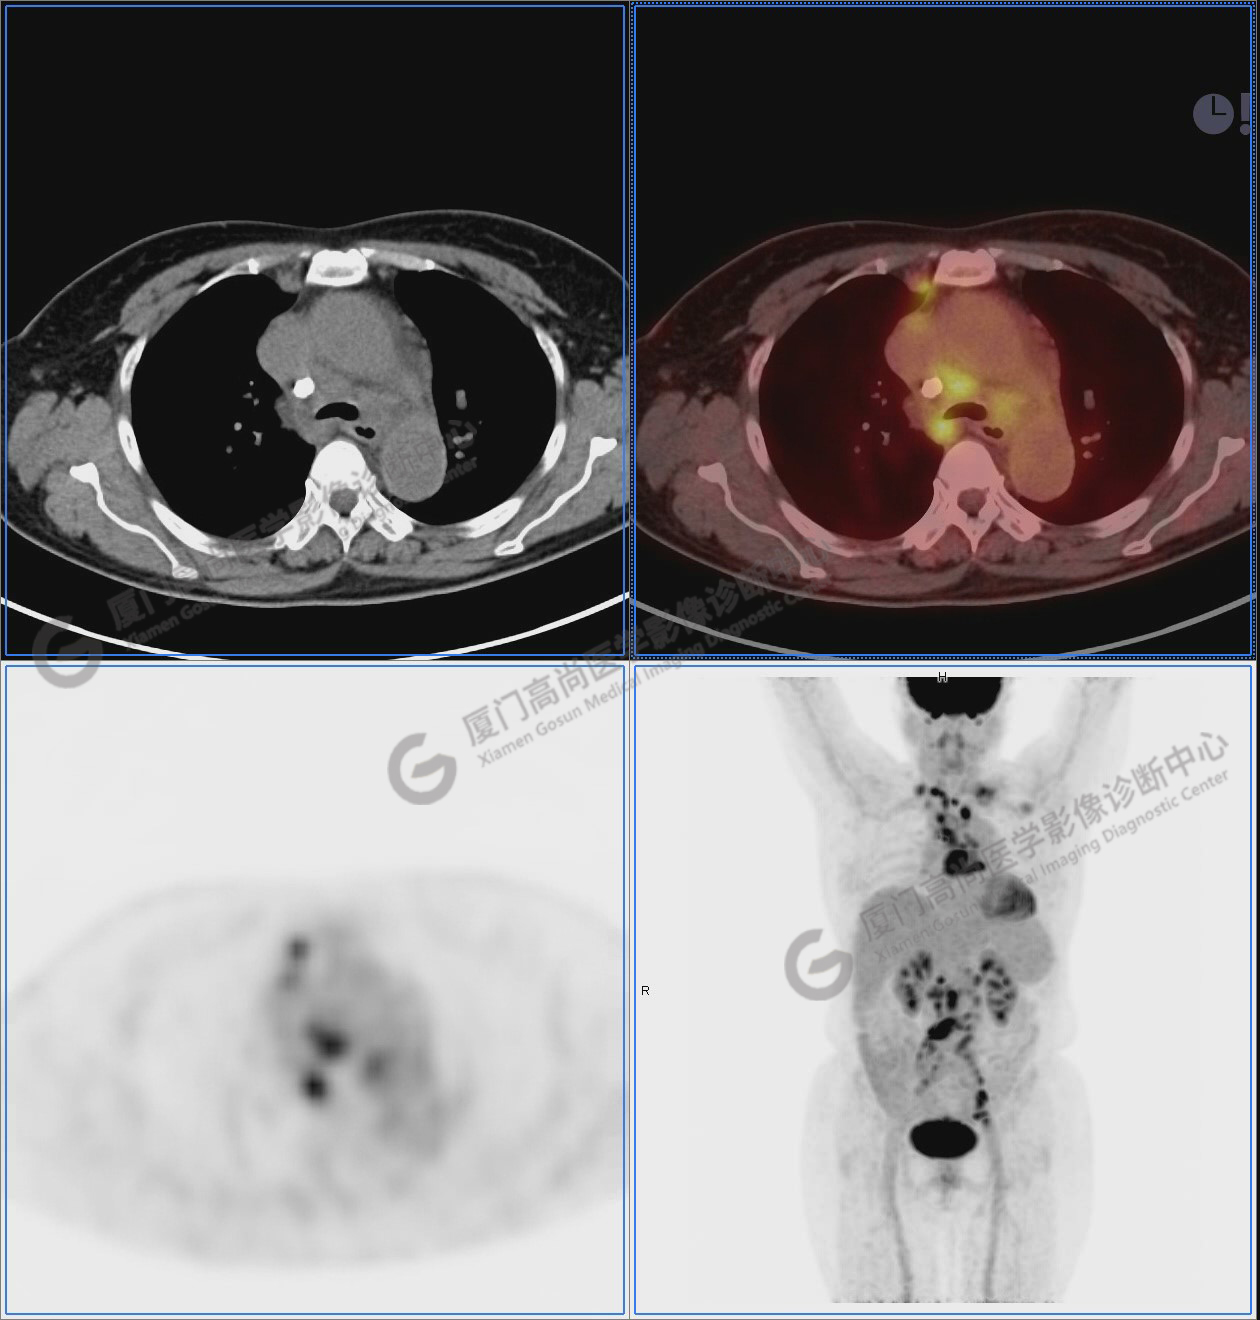

PET/CT影像圖

圖1:PET/CT全身圖像

圖2-9:雙側(cè)鎖骨區(qū)、縱隔、右側(cè)內(nèi)乳區(qū)、腸系膜緣、腹膜后、雙側(cè)髂血管旁及盆腔多發(fā)腫大淋巴結(jié)影,代謝不同程度增高,考慮為轉(zhuǎn)移。